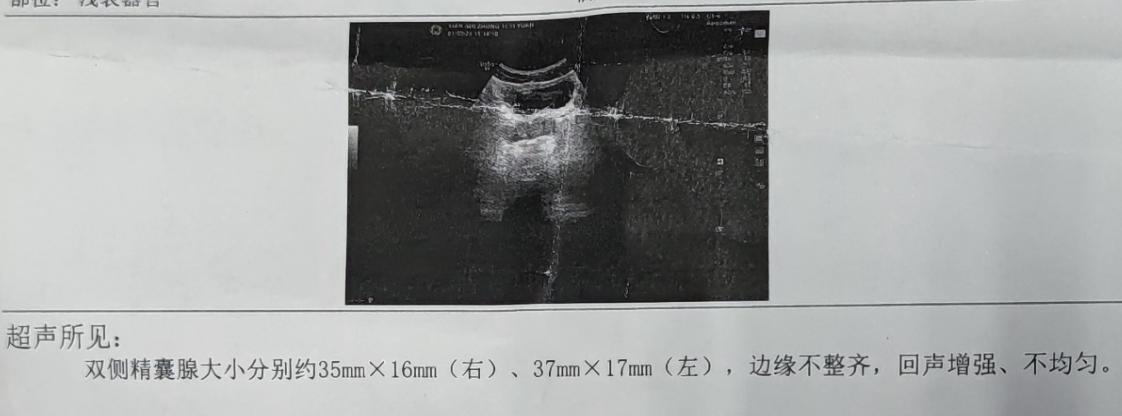

了解完患者病史后,安排患者完善了精液检查、尿常规、尿液分析、精囊腺超声等检查,排查有否存在炎症、器质性疾病,其中尿液分析结果回报无异常,精囊腺超声回报双侧精囊腺大小分别为35mm*16mm(右)、37mm*17mm(左),边缘不整齐,回声增强,不均匀,考虑炎性,精液检查可见大量红细胞。

因此,通过患者检查、症状、主诉,中医诊断为血精,西医诊断为精囊炎。患者血精主要是由于气血瘀阻、下焦湿热所致,所以治疗以去湿热、止血凉血为主。具体用药为裸花紫珠分散片消炎止血、银花泌炎灵片清热解毒,利湿通淋,以及黄芩片、白芍、藕节炭、地榆炭、当归、三七粉等水煎口服去湿热、止血。